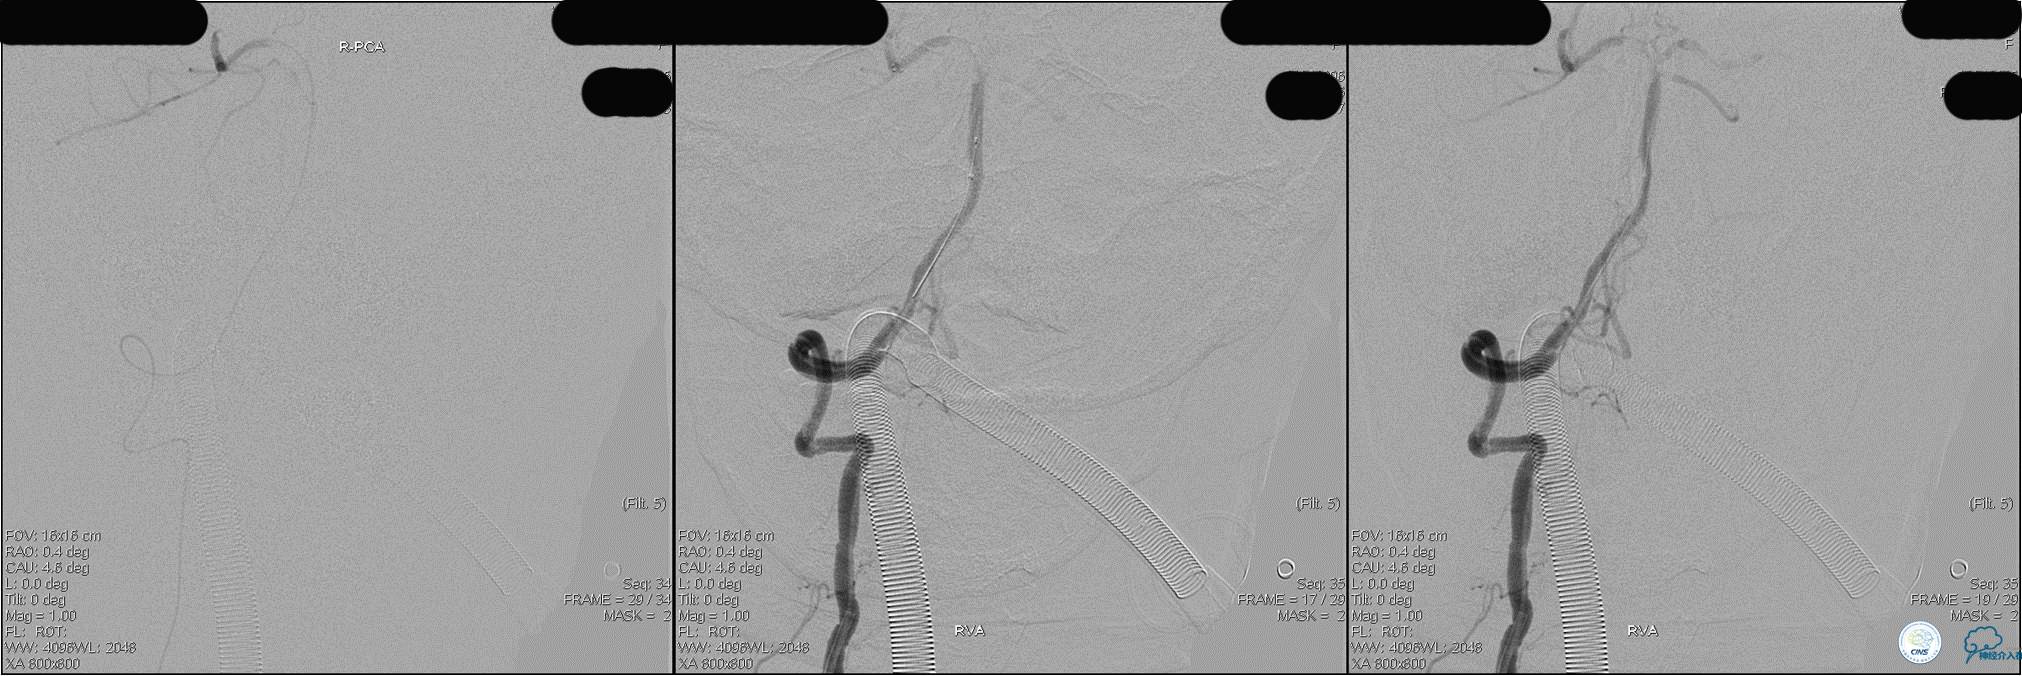

》DSA资料(第3次取栓)

第3次取出血栓

》DSA资料(第3次取栓后,发病10h)

★基底动脉尖端的血栓偏向哪侧,应该将Solitaire支架放入同侧的大脑后动脉,这样取栓的成功率较高一些。